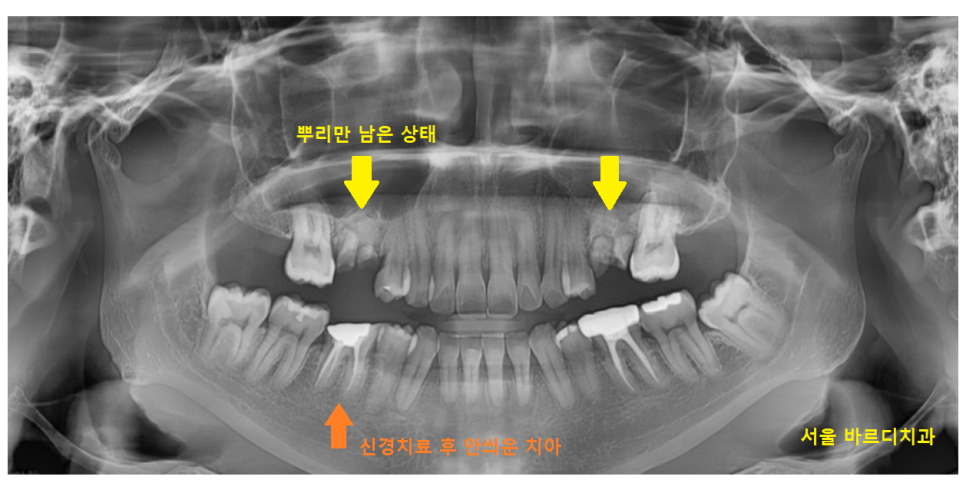

오른쪽 어금니의 경우

위 아래 모두 문제였지만

위에 치아의 경우

치아가 조각 조각 있죠~?

뿌리 개수 3개 형태가 남은것입니다.

머리는 다 썩어 없어졌네요.

이건 누가 와도 못살립니다.

발치 후

풍산동 임플란트를 흑흑